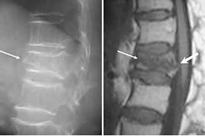

66歳女性:多発腰椎圧迫骨折

腰痛++で治療を継続しないと日常生活が困難です

左図:第3腰椎圧迫骨折

右図:脊椎固定術

2)X線圧迫骨折の定義:左から2番の脊椎X線像で、B/A=80%以下、C/A=75%以下が圧迫骨折。圧迫骨折=高度の骨粗鬆症を意味します。

骨粗鬆症+

中度圧迫骨折

(X線/MRI)